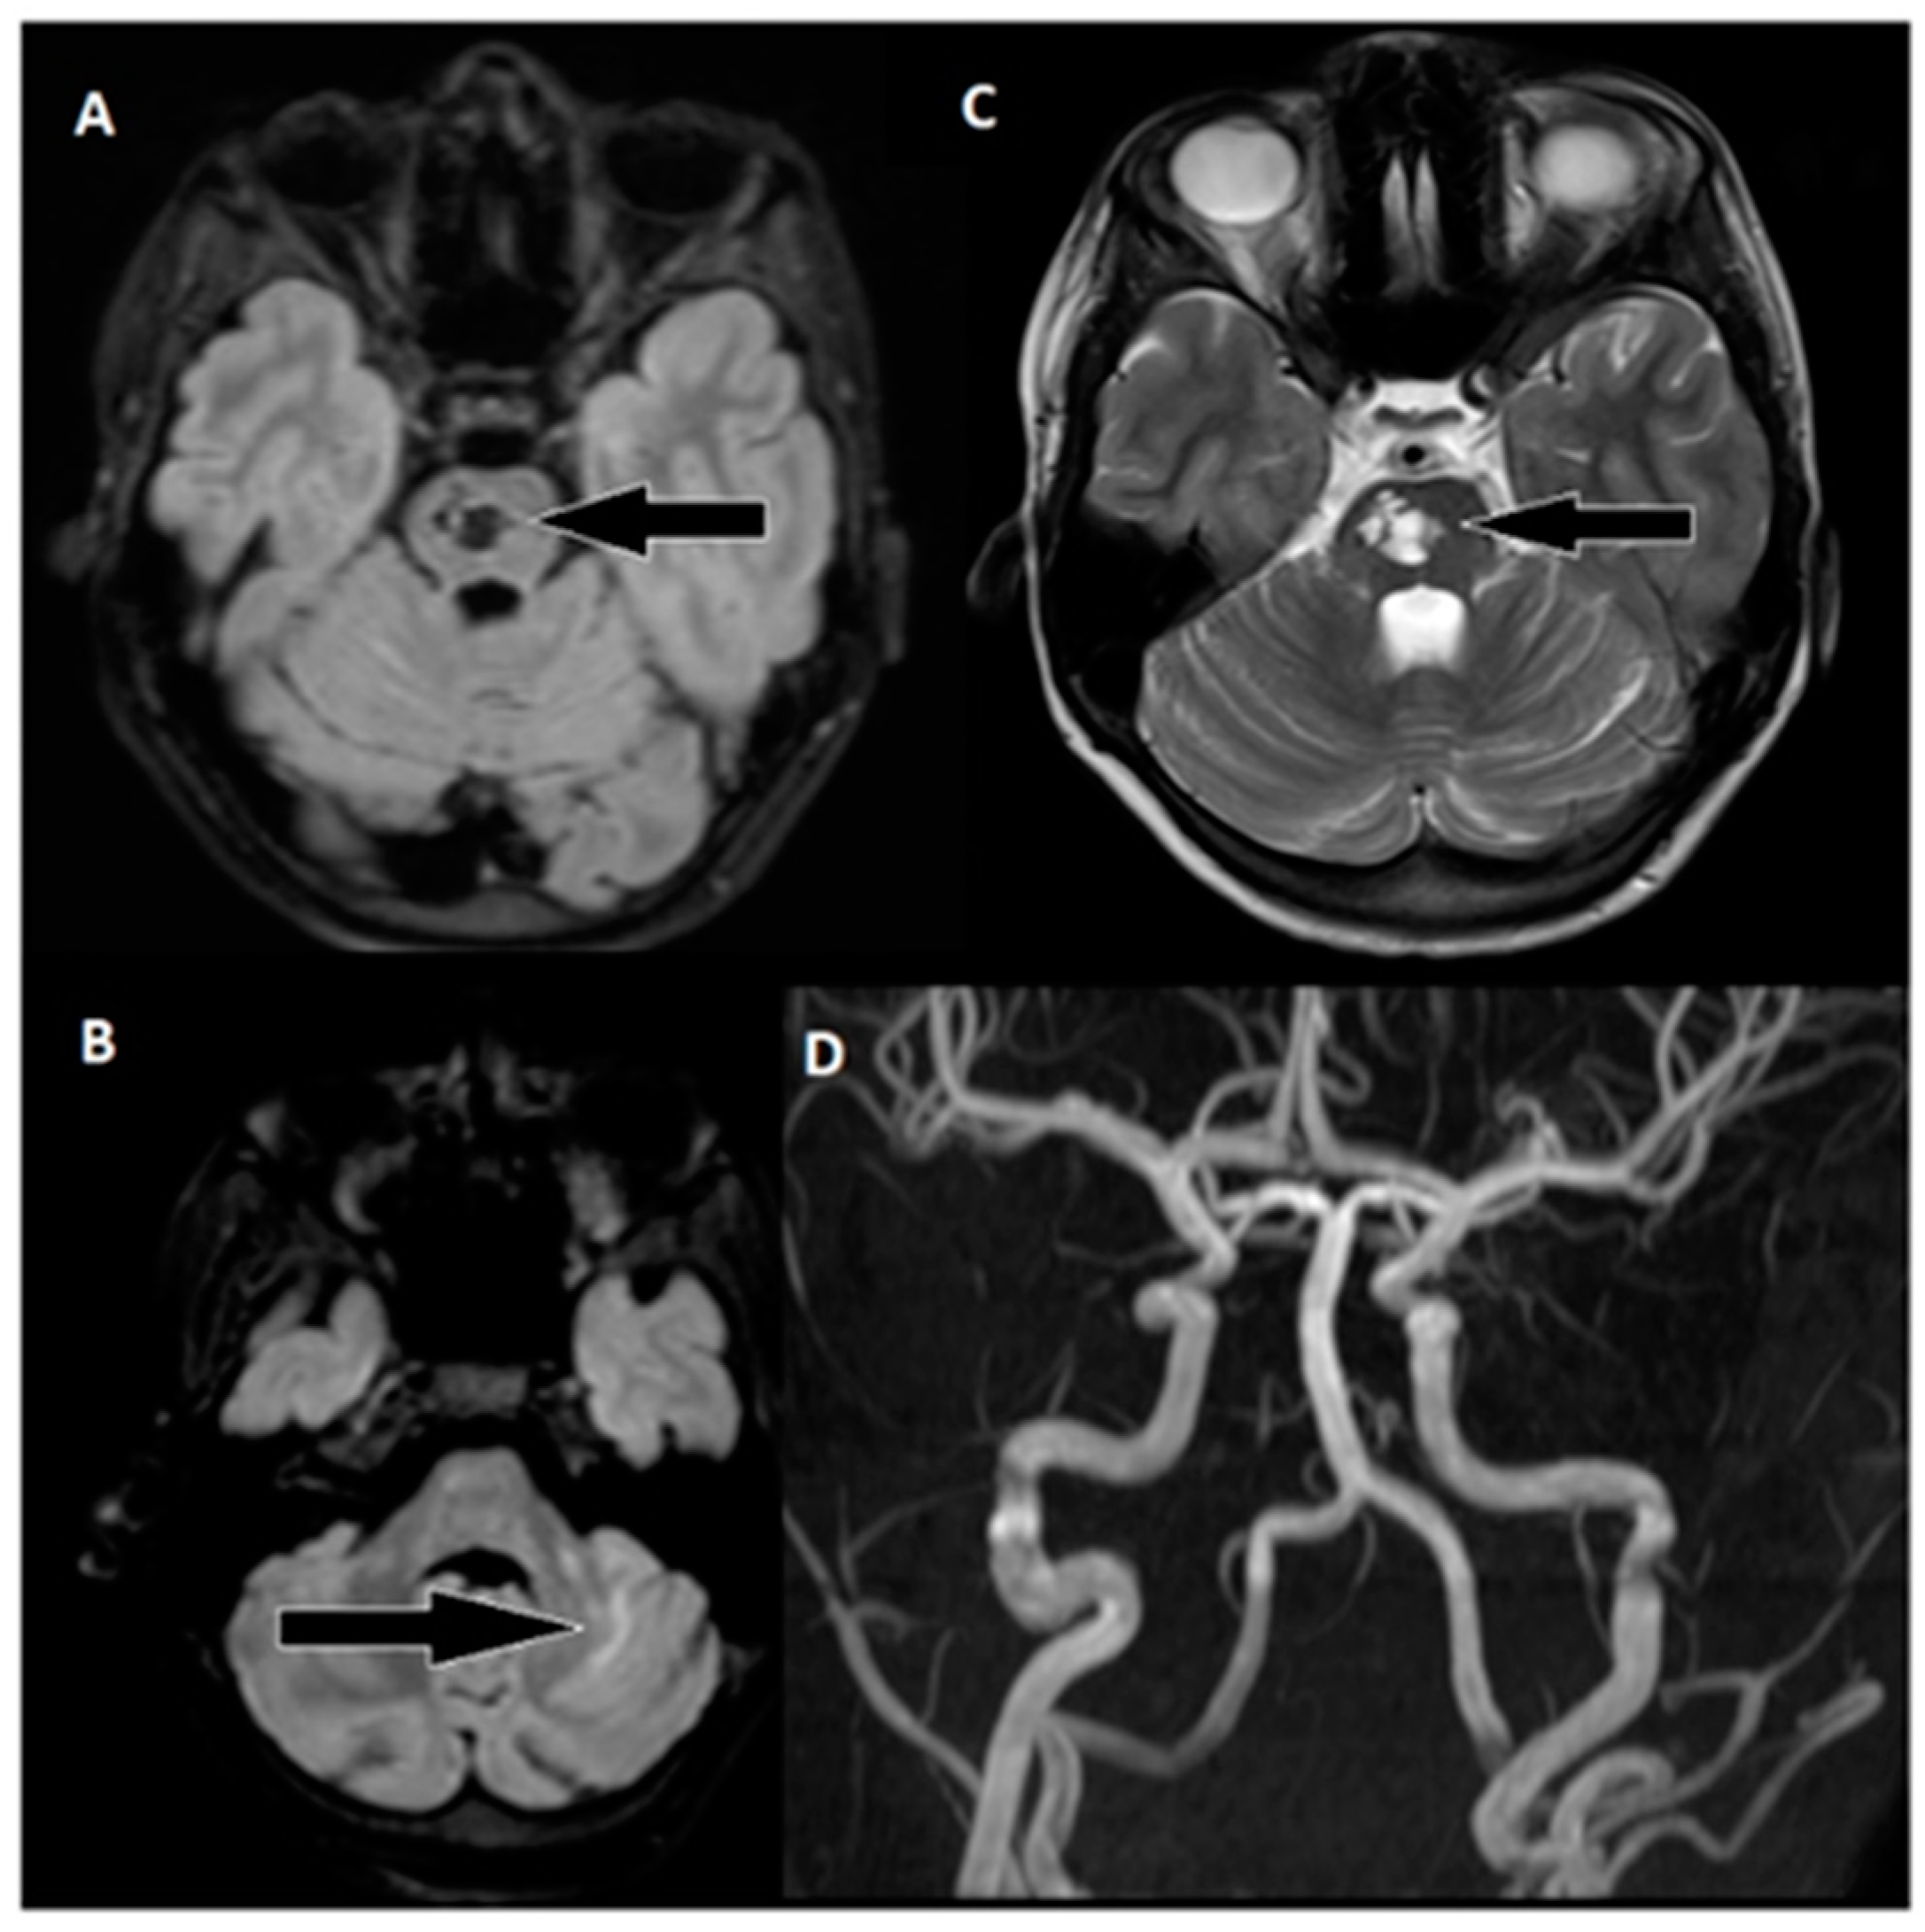

During the six-month follow-up, the patient exhibited a complete neurological recovery, as evidenced by an NIHSS score of 0 and an mRS score of 0. An MRI scan conducted at this time (Figure 6) revealed scarring with hypointense areas on the right pons in the FLAIR sequence. Importantly, magnetic resonance angiography (MRA) confirmed unobstructed flow in the basilar artery. This positive outcome marked a significant milestone in the patient’s journey toward recovery and underlined the remarkable resilience of the young patient in overcoming the challenges posed by this enigmatic stroke.

Figure 6. Follow-up MRI of the brain approximately 6 months after thrombectomy. (A) Markedly hypointense areas on the right side of the pons in the FLAIR sequence, indicating scarring. Corresponding hyperintense changes are observed on: (C) T2-weighted images, with a distinct hyperintense area on the right side of the pons (arrow). (B) Changes in the upper part of the left cerebellar hemisphere are visible in the FLAIR sequence. (D) An MRA examination shows unobstructed flow in the basilar artery and both cerebral posterior arteries.